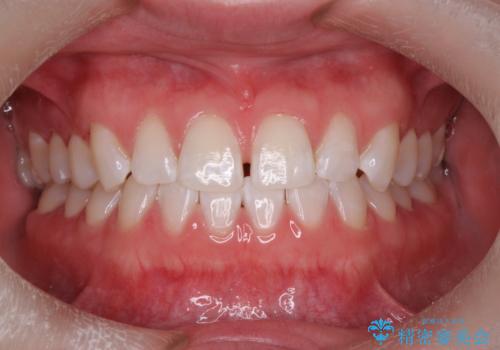

ワイヤー矯正中のクリーニング PMTC

- ワイヤー矯正中にクリーニングを行いたいとのことで来院されました。PMTC60分コースでと歯磨き指導も行いました。

ワイヤー矯正中はブラッシングが難しくなるため、磨き残しが多くなることがあります。適切な道具を使って、適切なブラッシング方法を習得することで、磨き残しを減らすことができます。

また、矯正で歯の移動があると今までなかったところに隙間が出てきたり、ガタつきが解消されてきたりすることで、お口の中の環境が変わります。そのため、定期的に専門的な機械・材料を使用したProfessinnalcleaning(pmtc)を行うことがおススメです。